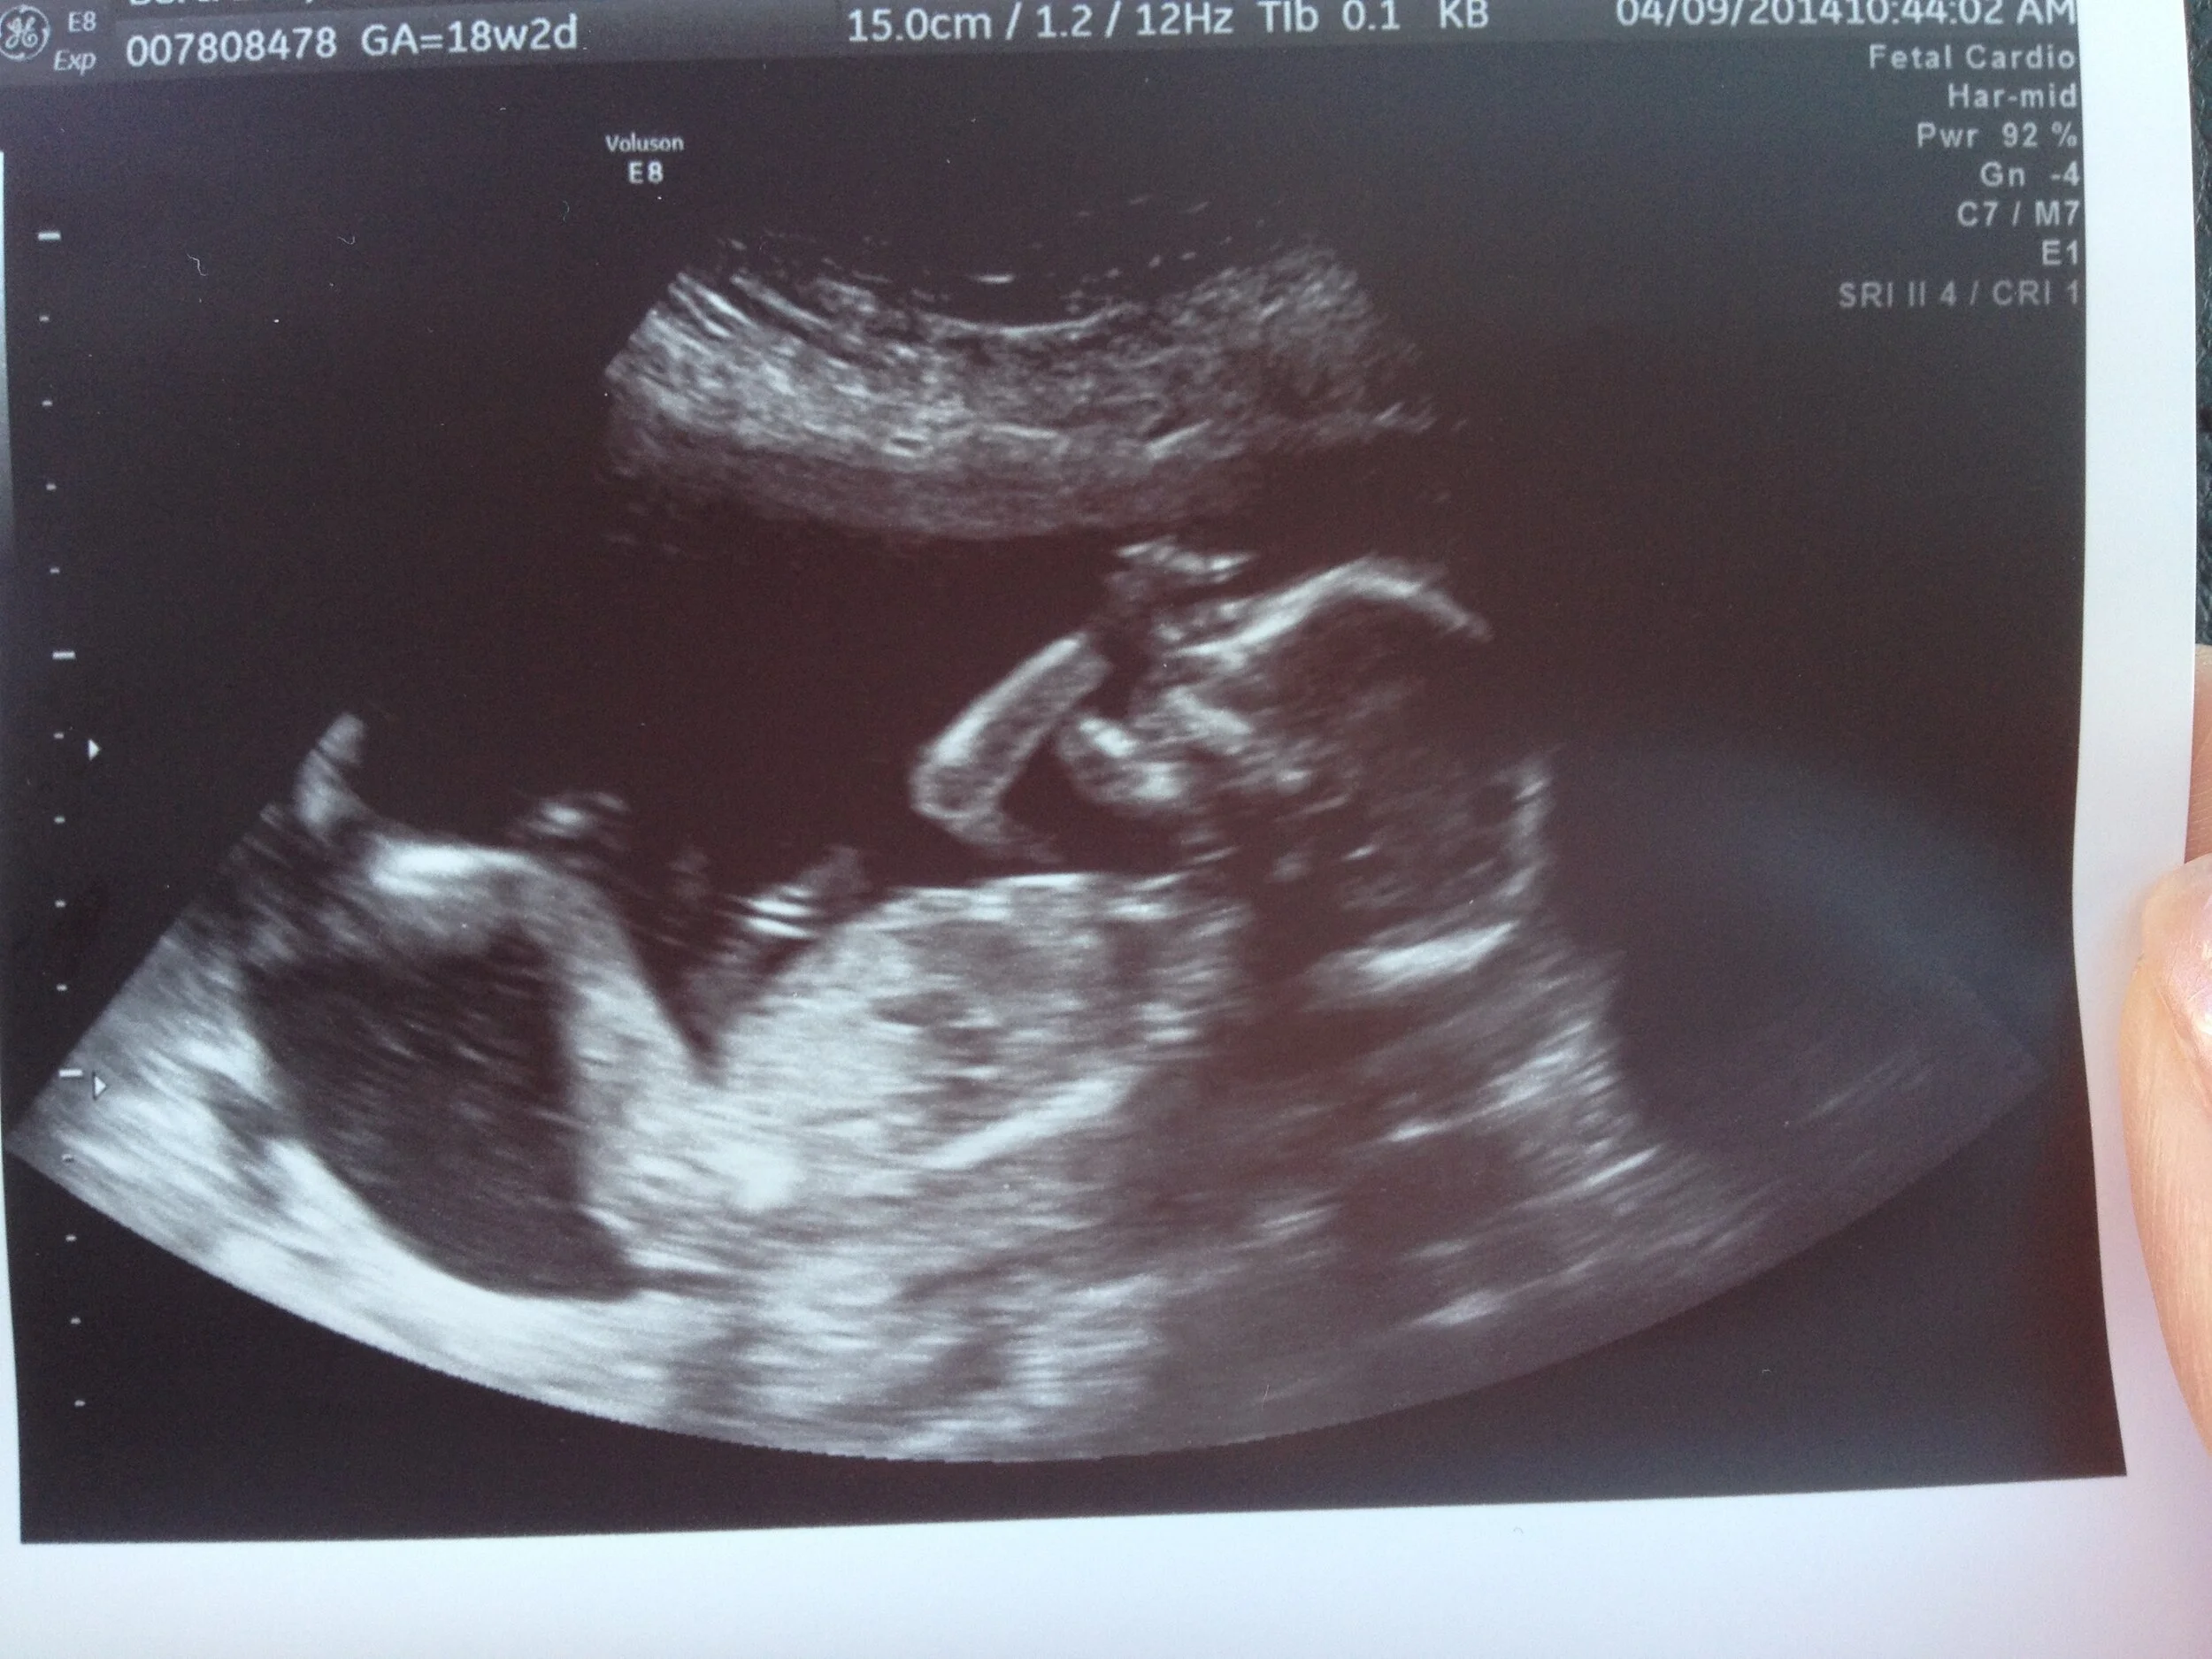

Almost 6 years ago to the day, I learned that we were pregnant with our second child. With one healthy pregnancy under my belt, I was confident there was little to nothing to worry about. Our daughter Madeline, a sweet, smart, energetic toddler, had entered the world exactly on her due date and at almost ten pounds. Hers was a trouble-free pregnancy. Growing a child was something I could do well, or so I thought. Because I had such a good pregnancy the first time, and got pregnant so easily this time, I told everyone. Immediately. I didn’t want to have to go through the annoying ritual of hiding it for 12 weeks this time around.

But this pregnancy was different right off the bat. I had no symptoms. Zero. Whereas, with my first pregnancy, I had sore breasts and was sick as a dog almost immediately. But my friends and family kept telling me that every pregnancy is different, so I tried to believe that everything was fine. But I knew something was wrong. A few weeks later, my husband Aaron and I had our first doctors appointment to confirm the pregnancy. During the ultrasound, the tech saw two embryos! We were having twins! But she said that one embryo was looking small and wanted the doctor to take a more in depth look. So she asked us to go back to the waiting room until the doctor was free. For the next 15 minutes, Aaron and I laughed at the thought of having two babies and all that would entail — two cribs, two car seats, a new car that could fit all 3 of our kids! And I started to think, “That’s why I didn’t have any symptoms…because this pregnancy really was different…there were two babies in there, not just one!”

When the doctor brought us in for the second ultrasound, she told us that we had what looked like a “vanishing twin”–which occurs when a twin disappears in the uterus during pregnancy as a result of a miscarriage of one twin. So we lost one baby. She told us that the other baby looked very small, about 5 weeks old (I was 8 weeks pregnant). Then she dealt the final blow and told us that because the baby was so small, she couldn’t see a heartbeat, and that this most likely meant that I would miscarry in the coming days. Then she sent us home.

About 2 weeks later I got my period, and 2 weeks after that I found out I was pregnant again. <3  Six years later, I of course still wonder what might have been, but then I also look at my sweet Nora (who’s now five) and realize I wouldn’t have her if I hadn’t have had my miscarriage. She’s my rainbow baby. She’s my miracle.